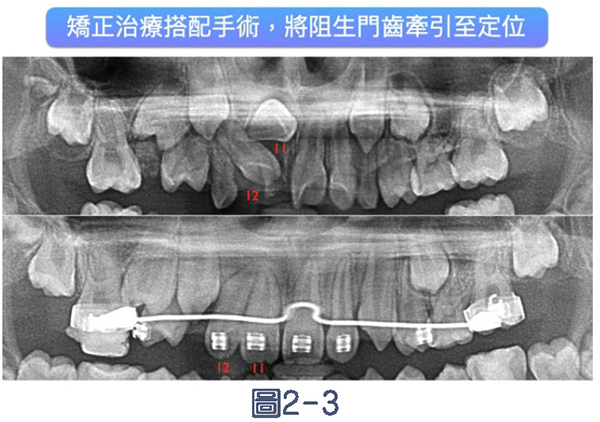

2.犬齒或其他阻生齒,早期接受矯正治療,並將阻生齒拉出:

上顎犬齒是口腔中萌發位置最複雜的恆牙之一。若犬齒因空間不足而發生阻生、未能順利萌出,可能會導致鄰近門牙根部吸收(見圖2-1),嚴重者甚至需拔牙處理。臨床上,透過早期X光診斷(見圖2-2)可及早發現犬齒阻生的潛在問題,若能在孩童約9至12歲階段介入治療,如移除乳牙、擴張牙弓或透過固定矯正裝置牽引犬齒順利萌出,不僅可避免牙根吸收的風險,也有助於建立完整且穩定的齒列結構。(見圖2-3、2-4)